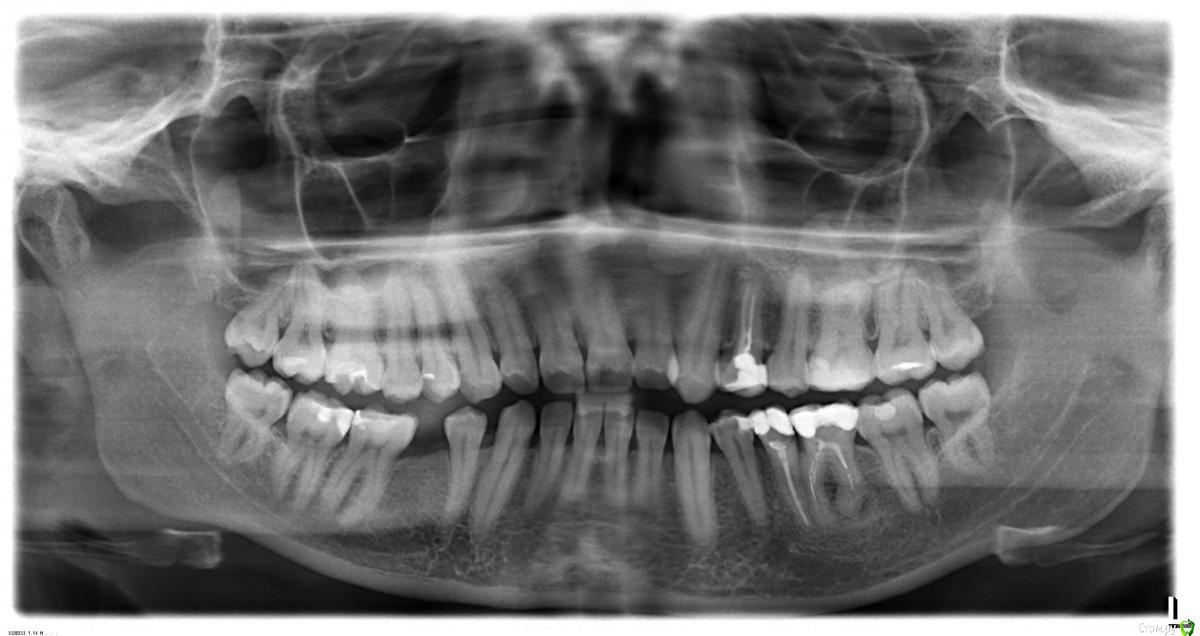

Здравствуйте! Нашли кисты/ гранулемы в зубах - 24

Подскажите , пожалуйста, есть ли там действительно воспаления , которые нужно лечить (нижний- понятно, что надо, сомнения насчет верхнего).

И если да - подскажите, огромная просьба, клиники, где мне качественно пролечат за меньшие деньги (желательно, конечно,под микроскопом)?